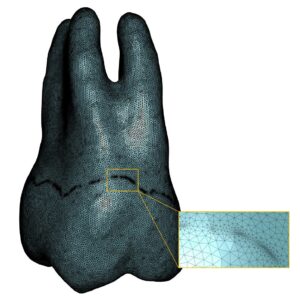

Highly detailed 3D model of a molar (approximately 1.3 million elements), created from medical imaging, enabling simulation of stress distribution within the tooth and its surrounding environment during mastication.